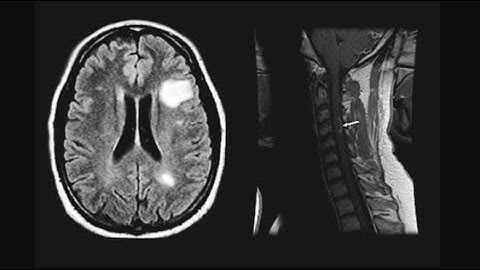

Understand Your Scan: Multiple Sclerosis MRI Cervical Spine